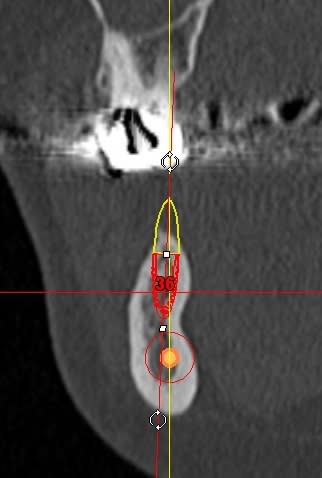

La rx avec bistouri en place sert à vérifier quoi?

la radio sert à vérifier la position de la lame 15, par rapport à la racine et au sinus, mais je ne suis pas sur que tu comprennes, que le bistouri est dans l'os, c'est l'instrument le plus fin et le moins traumatisant pour fendre l'os (je le préfère au piezzo et même au disque diamanté).